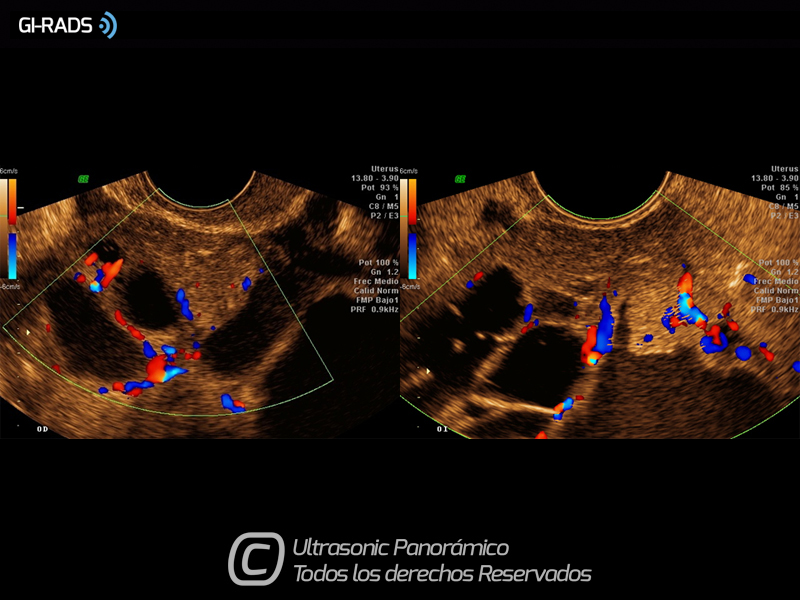

Cáncer Anexial – Flujo Abundante

• Cáncer Anexial – Flujo Abundante